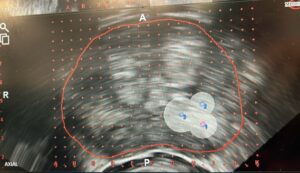

Foi recentemente realizado um procedimento de crioablação da próstata com recurso a software dedicado de planeamento e apoio clínico, uma tecnologia que contribui para aumentar a precisão no tratamento do cancro da próstata.

A crioablação é um tratamento minimamente invasivo em urologia que utiliza temperaturas extremamente baixas para destruir células tumorais na próstata. Com o apoio de software especializado e sistemas avançados de imagem, é possível planear e monitorizar o procedimento com maior rigor, permitindo uma abordagem mais direcionada e personalizada.

A utilização de ferramentas digitais no planeamento do procedimento permite identificar com maior detalhe as áreas a tratar, contribuindo para uma medicina de precisão no tratamento do cancro da próstata. Este tipo de tecnologia ajuda a otimizar a colocação das sondas de crioterapia e a monitorizar em tempo real a área de congelação, aumentando a segurança do procedimento.

A integração entre imagem médica, modelação tridimensional e software clínico representa um avanço significativo na prática da urologia moderna, permitindo melhorar os resultados clínicos e reduzir o impacto do tratamento para o doente.